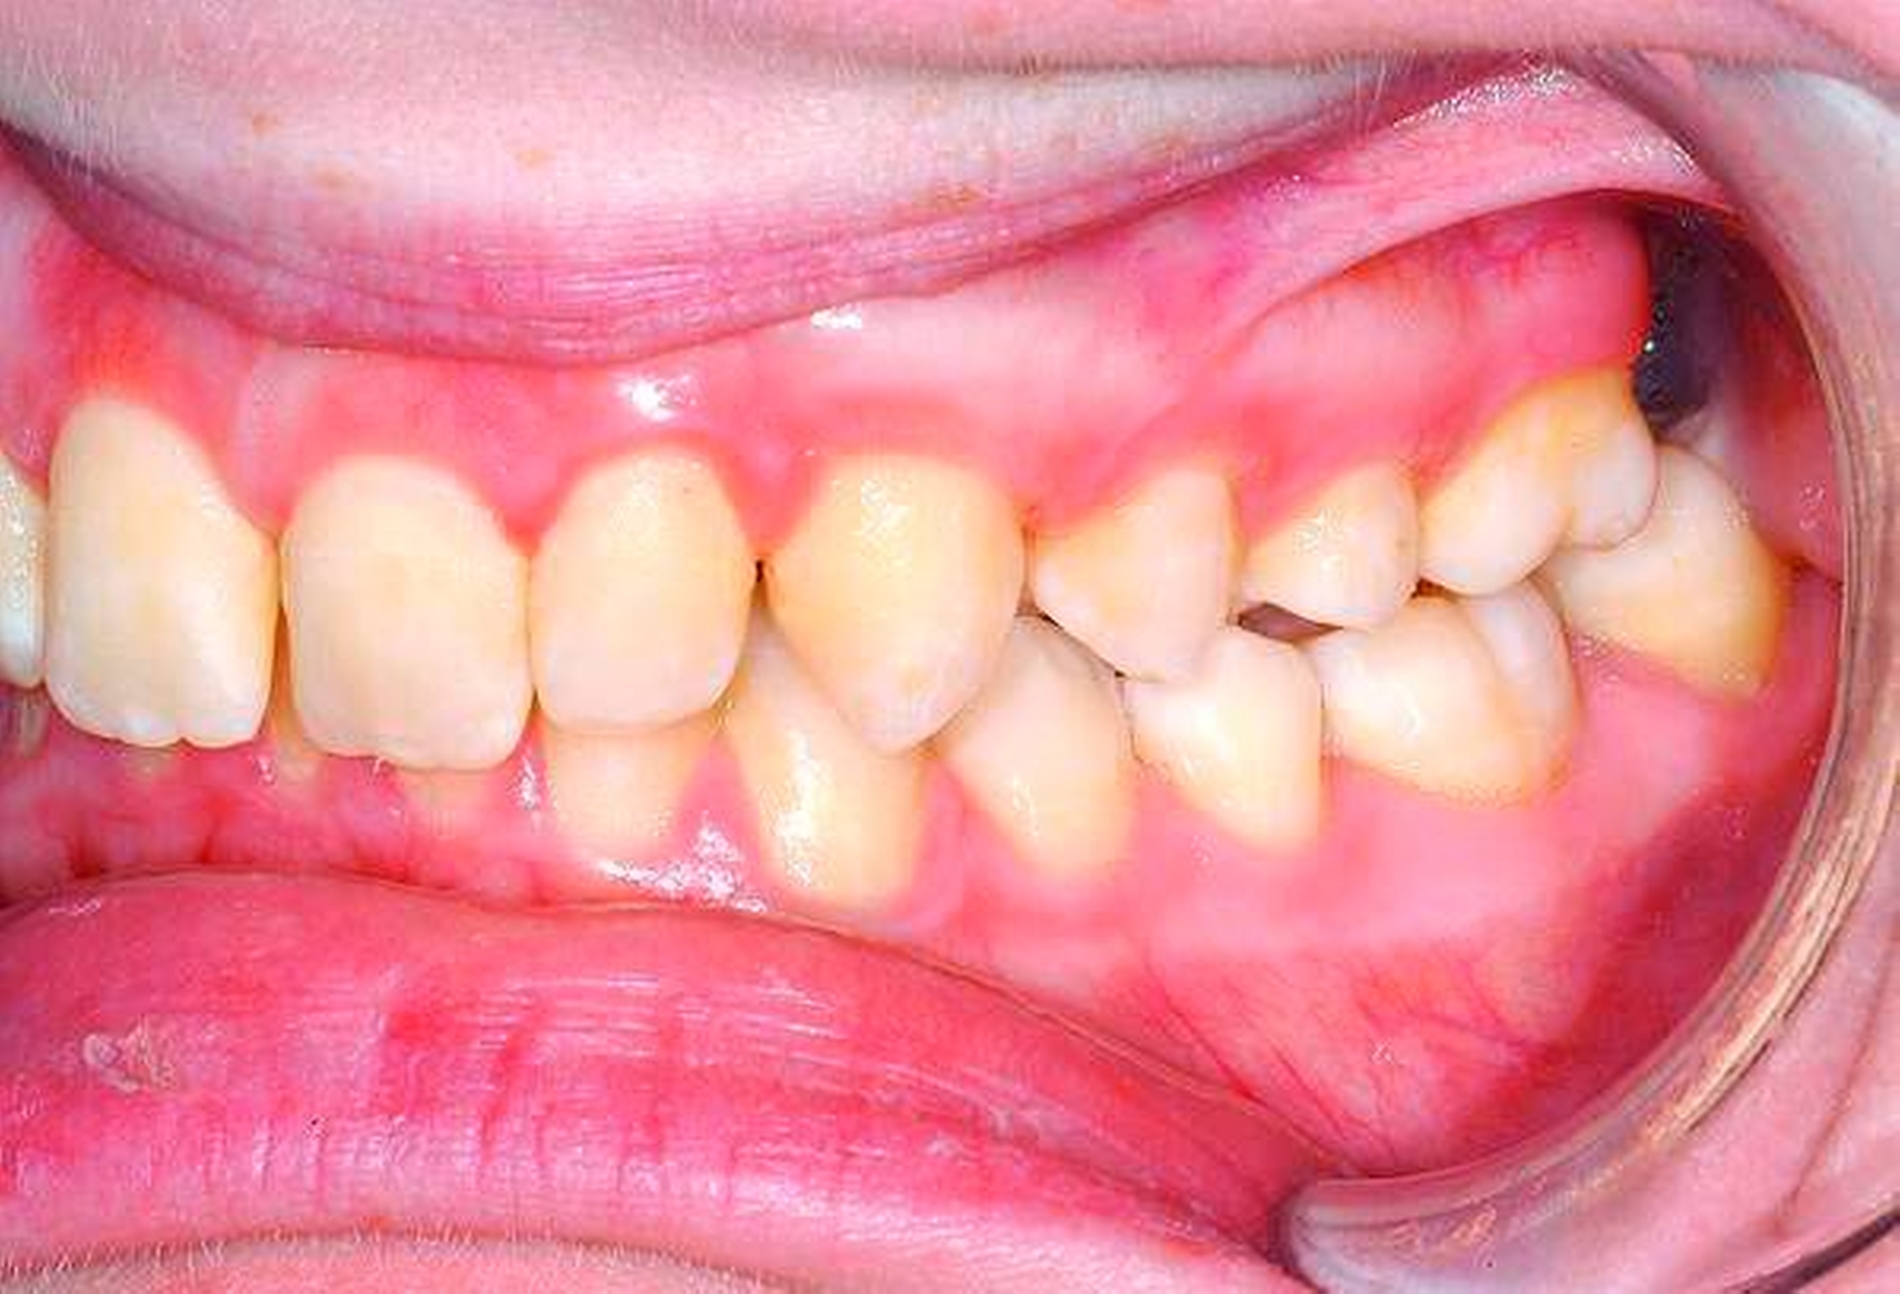

Eine 20-jährige Patientin wurde durch ihren Hauszahnarzt an unsere Poliklinik zur Entfernung aller Weisheitszähne überwiesen (Abbildung 1). Der Hauszahnarzt habe vergeblich versucht, diese zu extrahieren, die Lokalanästhesie habe keine ausreichende Wirkung erzielt.

Die Entfernung aller Weisheitszähne wurde schließlich nach einem weiteren frustranen Extraktionsversuch unter Lokalanästhesie in Intubationsnarkose durchgeführt, der postoperative Verlauf gestaltete sich komplikationslos, auffällige Blutungen traten nicht auf (Abbildungen 2 und 3).